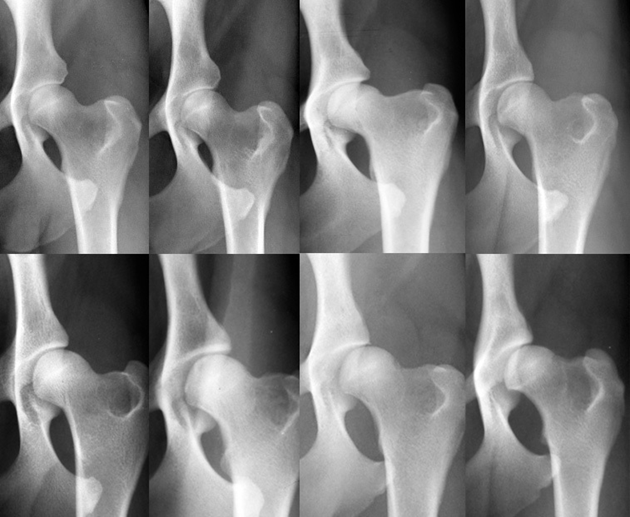

Die Diagnose HD lässt sich anhand von Röntgenaufnahmen des Hüftgelenks stellen. Sichtbare Veränderungen können an der Gelenkspfanne, am Oberschenkelkopf oder an beiden Knochen auftreten. Bei jungen Hunden ist gelegentlich nur ein auffällig lockeres Hüftgelenk zu beobachten, bei dem der Oberschenkelkopf nicht korrekt in der Gelenkspfanne liegt.

Aufgrund der Veränderungen auf dem Röntgenbild werden fünf Schweregrade von HD unterschieden.

Abb. 1: Verschiedene Hüftgelenke, von A, normal bis E, hochgradig dysplastisch (Bildfolge Dr. A. Vezzoni, mit bestem Dank).